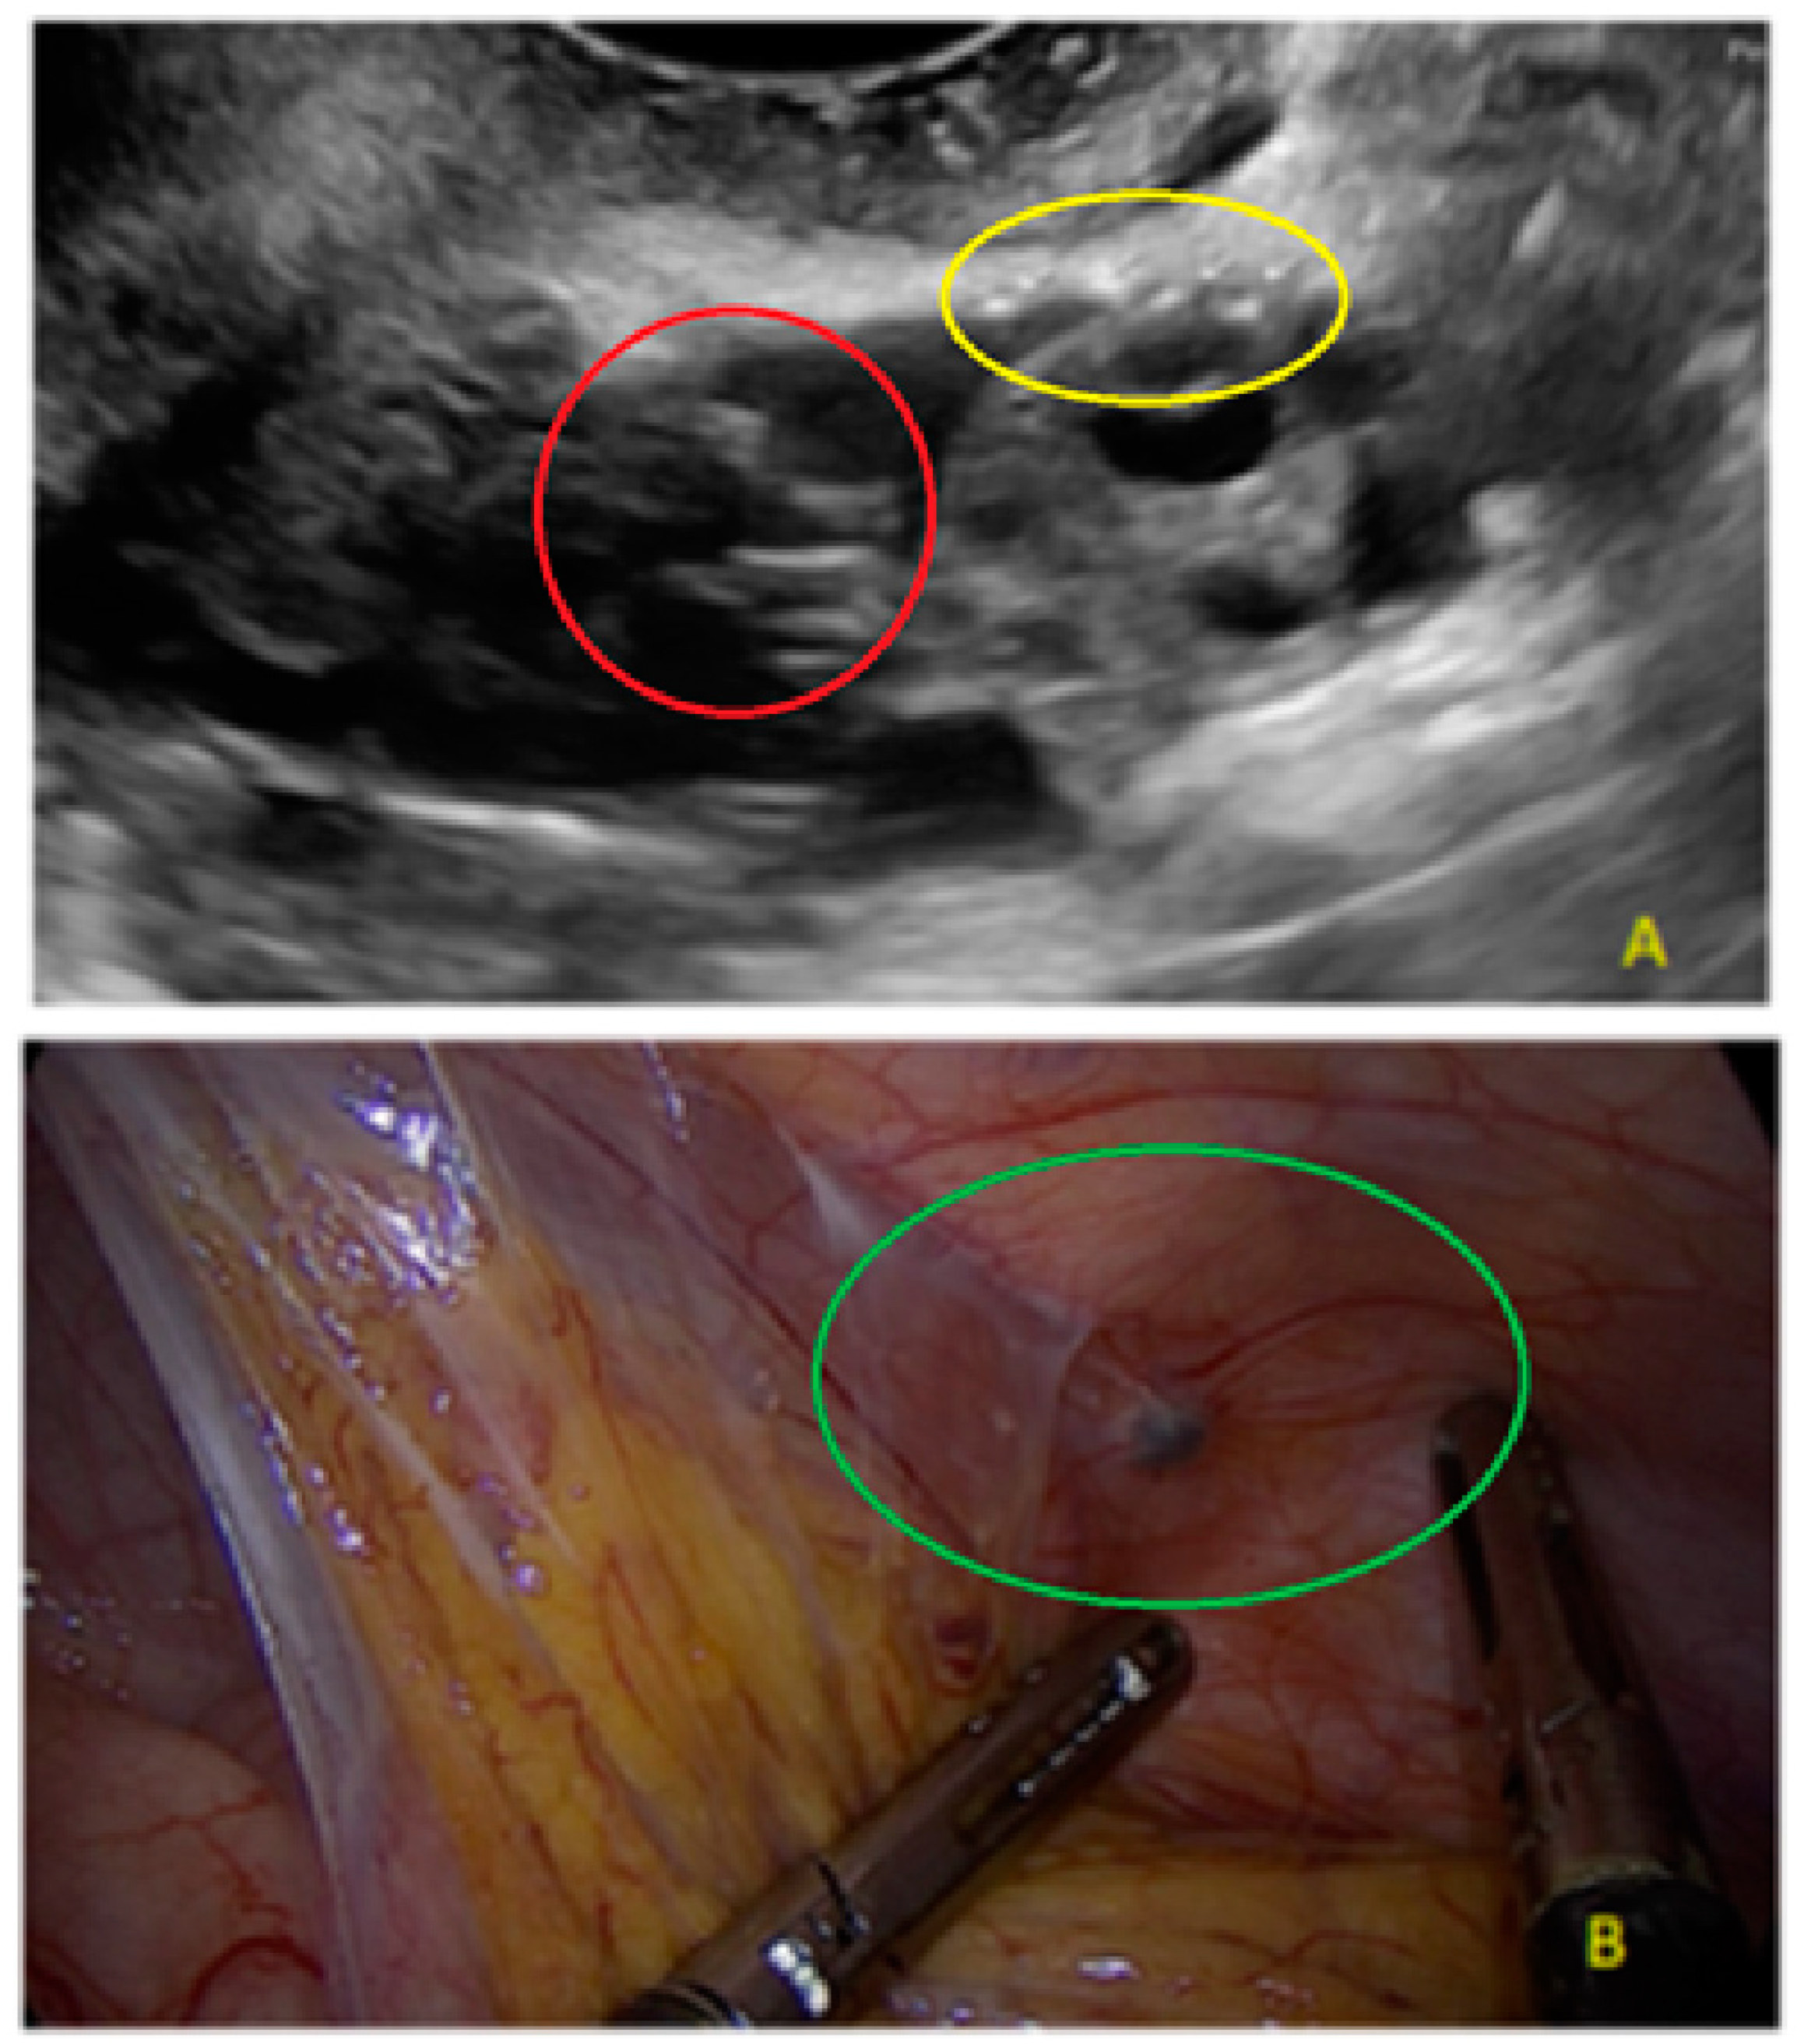

- The presence of velamentous (filmy) adhesions associated to the lesion (we called this a “veil”).

- The lesion may be convex, protruding from the peritoneal surface into the peritoneal cavity (we called this “bulging”), or it may appear as a concave defect in the peritoneum (we called this a “pocket”).

3.1. Cystic Solitary Lesion

3.2. Cystic Multiple Separate Lesions

3.3. Cystic Lesions Arranged in a Cluster